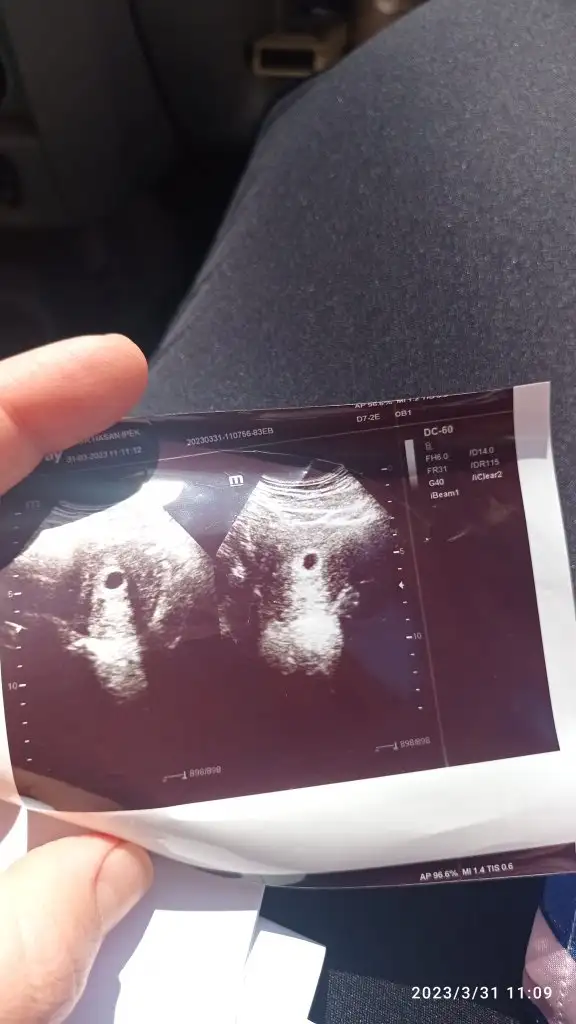

Bende ilk ultrason muayenesi oldun nasip olursa kasima anne adayiyim. Kese gordu ama bebek yok 6+6 dayiz ama bebek olusuma baslamis cikintisi var dedi

Kese boyu kaç çıktı acaba? Ben de bugün gideceğim 6+3üm. Keseyi geçen hafta götürmüştük, bu hafta bebeği ve kalp atışını görmek için çağırdı da

Bende salı keseyi gördüm 10 mmdi 15 gün sonra gel dedi doktor inşallah görürüm bebişi